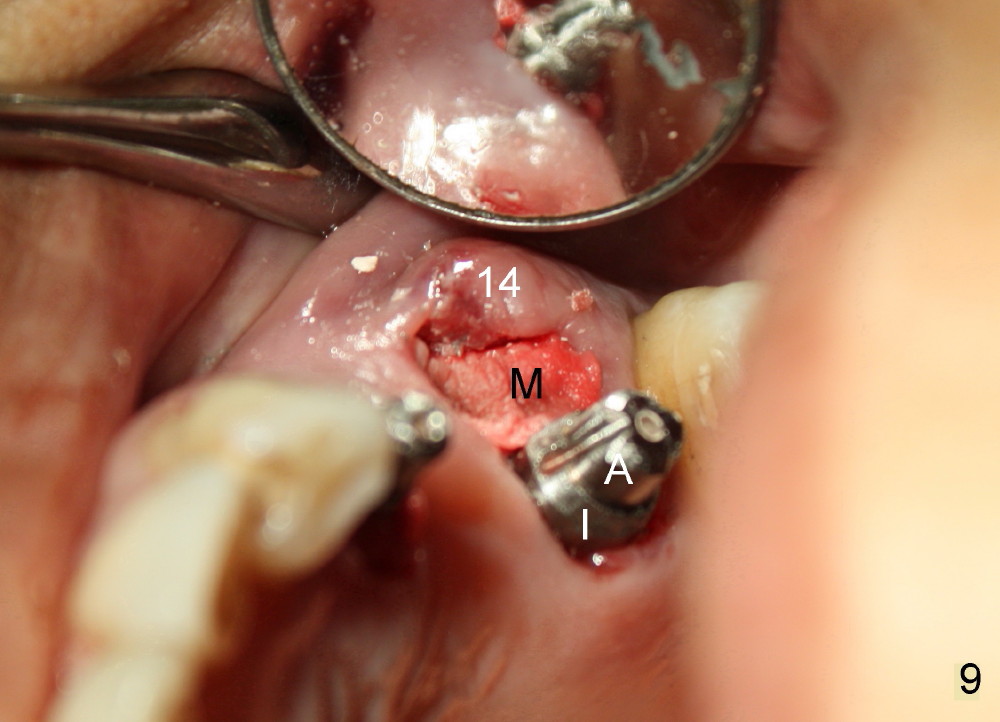

Buccal to #14 implant/abutment is a large defect, which is filled with allograft and Osteogen and covered by collagen membrane (Fig.9 M). The defect at the site of #12 is mesiopalatal, which is repaired in the same fashion (Fig.10: M). The collagen membrane is in turn protected by the "overhang" (extension) of the immediate provisional bridge (Fig.11,12 *). Once the wounds heal (Fig.13, 9 days postop), the extension is trimmed (Fig.14).